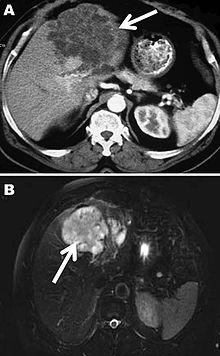

A formal diagnosis of any type of echinococcosis requires a combination of tools that involve imaging techniques, histopathology, or nucleic acid detection and serology. For cystic echinococcosis diagnosis, imaging is the main method—while serology tests (such as indirect hemogglutination, ELISA (enzyme linked immunosorbent assay), immunoblots or latex agglutination) that use antigens specific for E. granulosus verify the imaging results. The imaging technique of choice for cystic echinococcosis is ultrasonography, since it is not only able to visualize the cysts in the body's organs,[21] but it is also inexpensive, non-invasive and gives instant results.[22] In addition to ultrasonography, both MRI and CT scans can and are often used although an MRI is often preferred to CT scans when diagnosing cystic echinococcosis since it gives better visualization of liquid areas within the tissue.[21]

As with cystic echinococcosis, ultrasonography is the imaging technique of choice for alveolar echinococcosis and is usually complemented by CT scans since CT scans are able to detect the largest number of lesions and calcifications that are characteristic of alveolar echinococcosis. MRIs are also used in combination with ultrasonography though CT scans are preferred. Like cystic echinococcosis, imaging is the major method used for the diagnosis of alveolar echinococcosis while the same types of serologic tests (except now specific for E. multilocularis antigens) are used to verify the imaging results. It is also important to note that serologic tests are more valuable for the diagnosis of alveolar echinococcosis than for cystic echinococcosis since they tend to be more reliable for alveolar echinococcosis since more antigens specific for E. multilocularis are available.[13] In addition to imaging and serology, identification of E. multilocularis infection via PCR or a histological examination of a tissue biopsy from the person is another way to diagnose alveolar echinococcosis.[21]